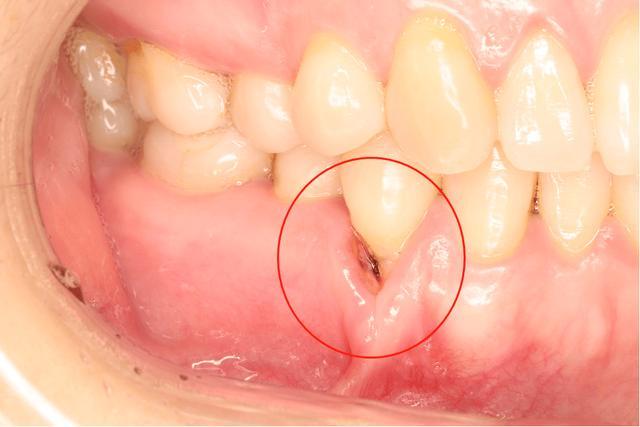

1、牙齦紅腫:牙周炎患者的牙齦組織通常會變得紅腫。

2、牙齦出血:刷牙或咬硬物時容易出血。

5、牙齒松動:炎癥嚴重時,可能導致牙齒松動。

1、診斷:牙醫(yī)會通過檢查牙齒和牙周組織,以及詢問癥狀來診斷牙周炎,可能需要進行X光檢查以評估牙槽骨的狀況。